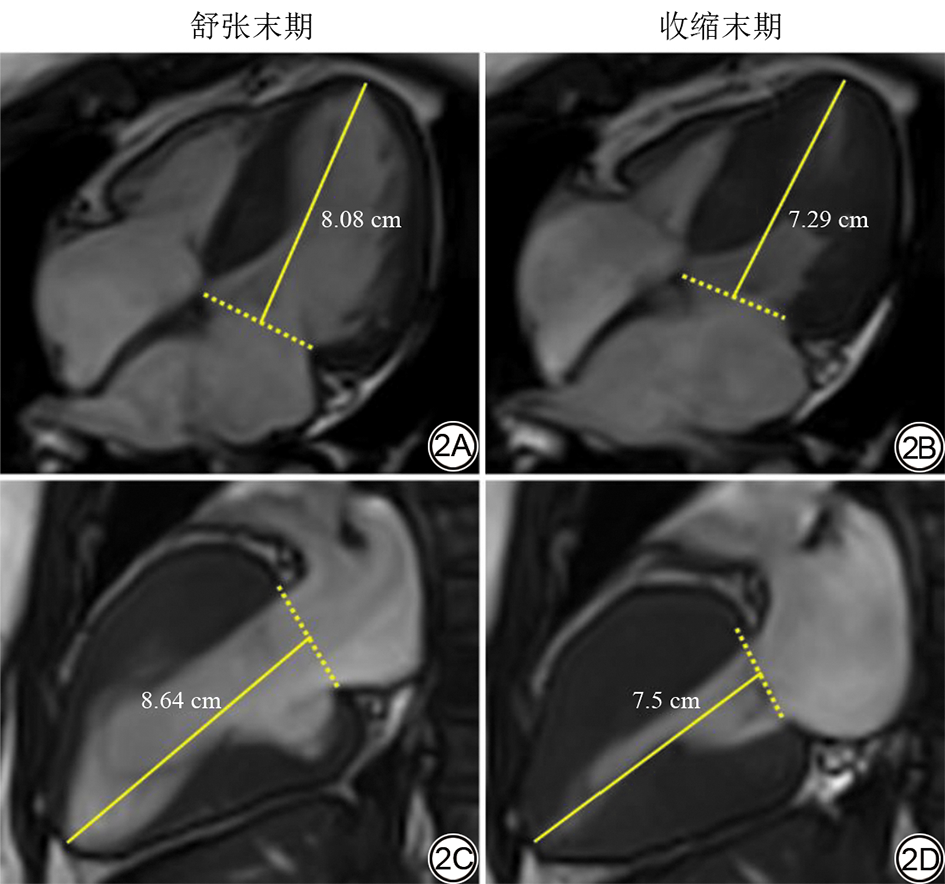

FLAS的测量参照既往文献所描述的方法进行[21, 24]。在左心室长轴两腔心及四腔心电影序列上,分别于收缩末期和舒张末期测量左室心尖心外膜边界至二尖瓣叶附着点连线中点的距离。FLAS计算公式为:FLAS=[(收缩末期距离-舒张末期距离)/舒张末期距离]×100%。每个切面重复测量3次,最终结果取两切面所测值的平均值(图2)。

图2  FLAS测量示意图。52岁,女,HCM患者。2A:四腔心舒张末期;2B:四腔心收缩末期;2C:两腔心舒张末期;2D:两腔心收缩末期。测得FLAS为-11.5%。FLAS:快速长轴应变;HCM:肥厚型心肌病;CMR:心脏磁共振。

Fig. 2  Schematic diagram of FLAS measurement. A 52-year-old female HCM patient using CMR cine images. 2A: End-diastolic four-chamber view; 2B: End-systolic four-chamber view; 2C: End-diastolic two-chamber view; 2D: End-systolic two-chamber view. The measured FLAS is -11.5%. FLAS: fast long-axis strain; HCM: hypertrophic cardiomyopathy; CMR: cardiac magnetic resonance.